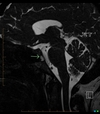

Ecchordosis Physaliphora

Cystic lesion in the prepontine cistern without enhancement or restricted diffusion extending into bone.

Absence of enhancement or restricted diffusion together with non-aggressive bony margins in this location is typical of a retroclival ecchordosis physaliphora, a notochord remnant.

Ecchordosis physaliphora is a congenital benign hamartomatous lesion derived from notochord remnants, usually located in the retroclival prepontine region, but can be found anywhere from the skull base to the sacrum.